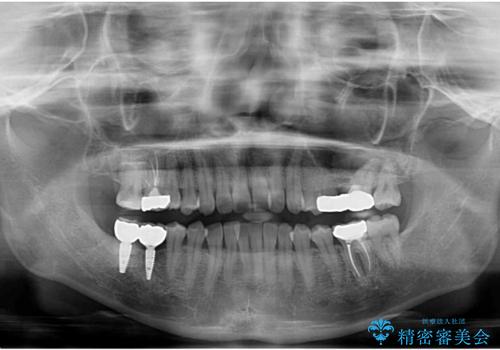

右上に部分矯正を行い、クリアランスを確保した後、右下にイプラントを2本埋入しています。

上の歯が伸びだしてきていたため、部分矯正を行い歯を移動させてから、向かい合わせの歯にインプラント治療を行っています。

右上第一大臼歯は六本木院の林院長に根管治療をお願いしました。